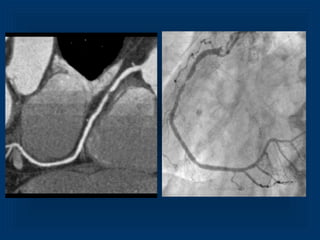

Maximum Intensity Projection RCA 3D VRT LCX and RCA

Maximum Intensity ProjectionRCA 3D VRT LCX and RCA